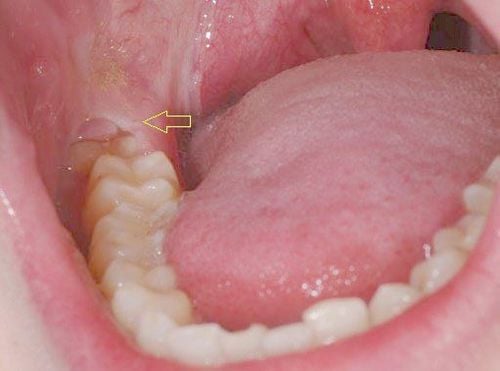

2. Gây sâu và phá hủy răng số 7 (Hậu quả đáng tiếc nhất)

Đây là hậu quả nghiêm trọng và gây nhiều hối tiếc nhất. Răng khôn mọc nghiêng, húc vào răng số 7 tạo ra một vị trí giắt thức ăn không thể làm sạch. Theo thời gian, axit do vi khuẩn sinh ra sẽ ăn mòn, gây ra một lỗ sâu lớn ở mặt sau của răng số 7 – vị trí khó phát hiện và rất khó để trám.

💡 Cảnh báo từ chuyên gia (Experience): Răng số 7 là một trong những răng ăn nhai chính và quan trọng nhất. Rất nhiều trường hợp, khi phát hiện ra thì lỗ sâu ở răng số 7 đã quá lớn, ăn vào tủy, thậm chí vỡ lớn không thể giữ lại. Cuối cùng, bạn không chỉ phải nhổ răng khôn, mà còn mất luôn cả chiếc răng số 7 quý giá bên cạnh. Hy sinh một chiếc răng vô dụng để cứu một chiếc răng trụ cột là một quyết định khôn ngoan. -